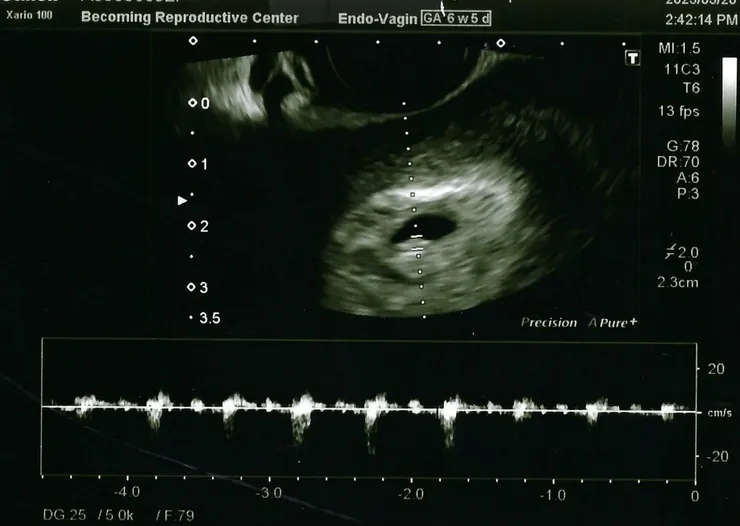

所幸,當天植入的兩顆胚胎中,有一顆順利著床,目前懷孕六週又一天,並已可見胎兒心跳,令人振奮!